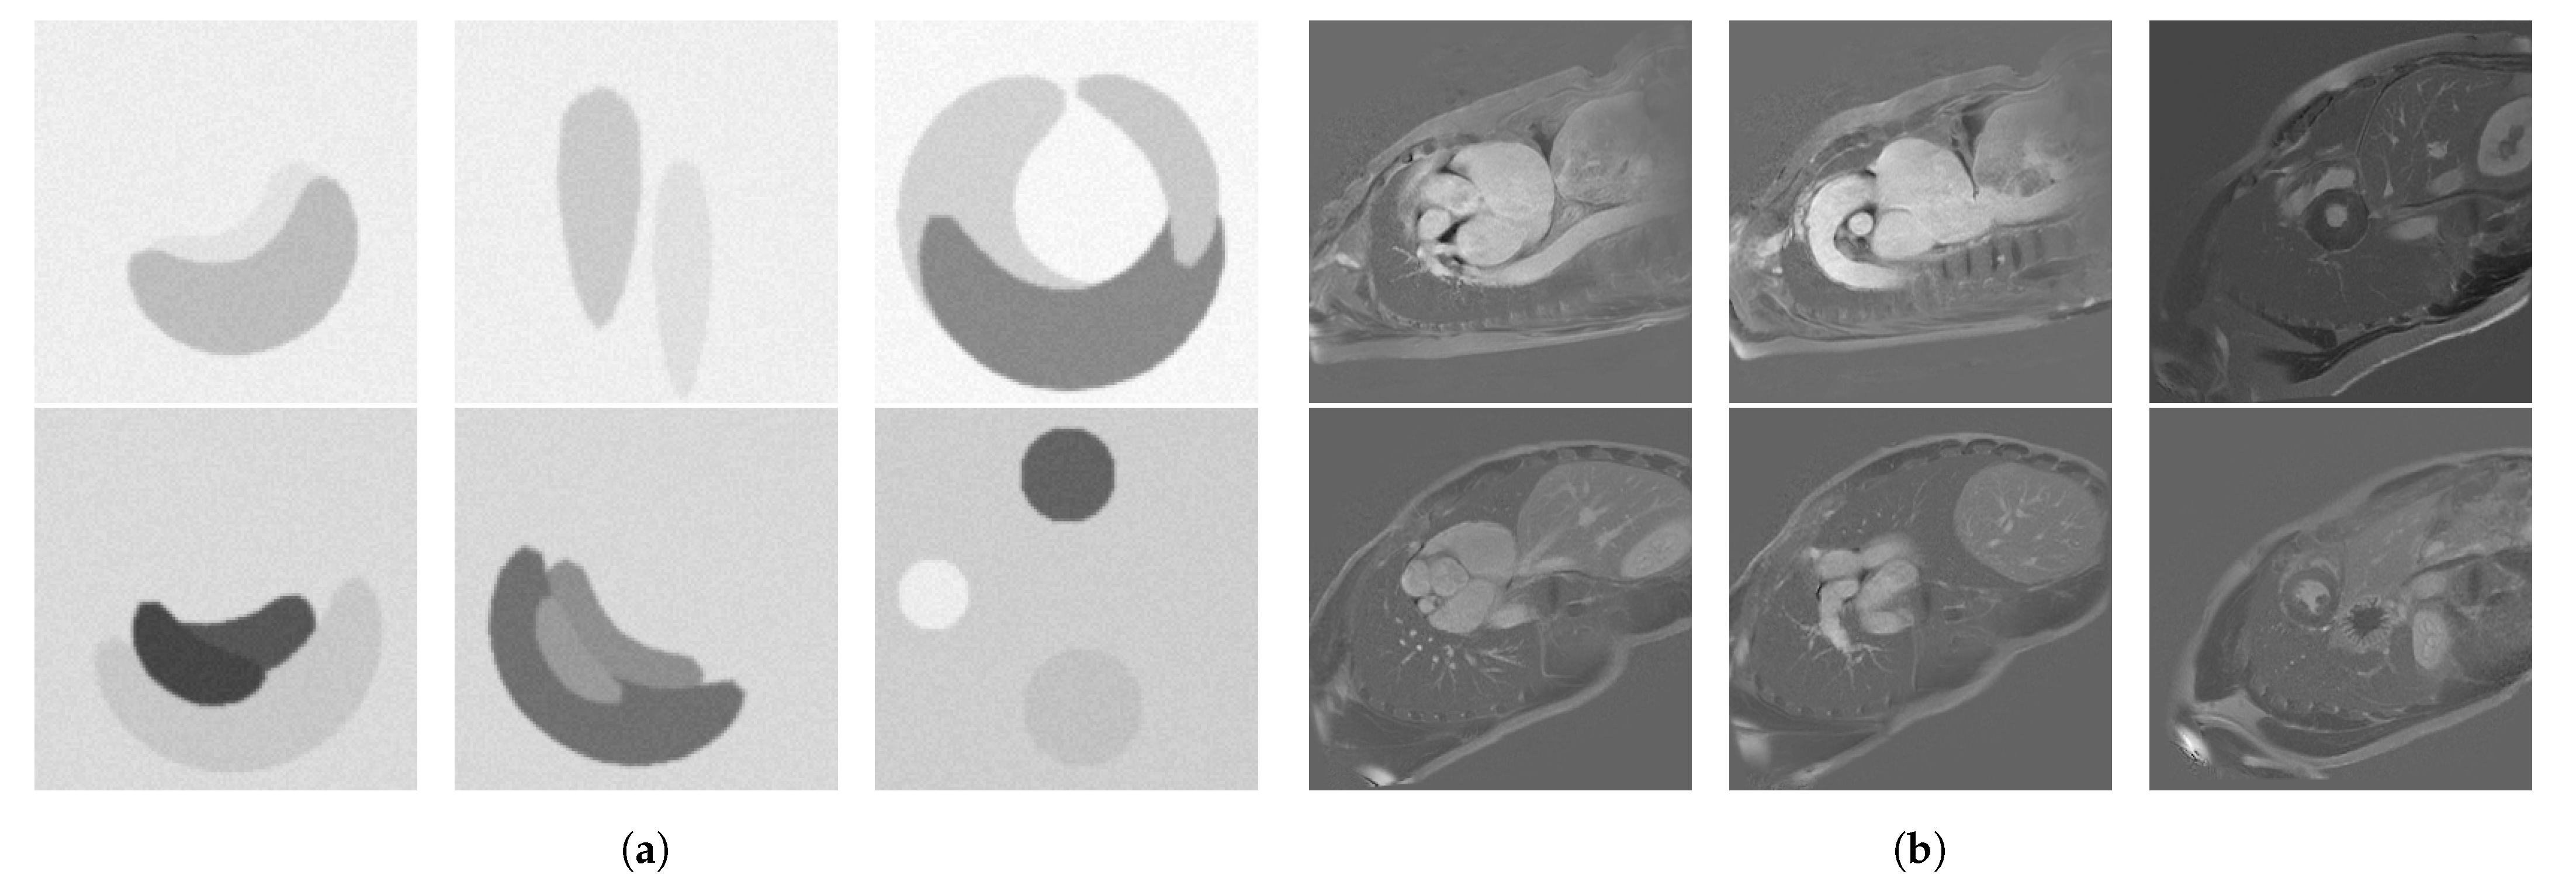

Upon visual assessment, we split the available MRI slices based on grey levels in two separate test sets, which we call low intensity and high intensity, respectively. To validate this split, we computed the average signal-to-noise ratio (SNR) over each resulted test set, and we obtained 2.570 ± 0.869 for the low intensity and 10.571 ± 3.66 for the high intensity set. The test sets contain 132 low intensity and 328 high intensity cardiac MRI slices from 32 patients and healthy volunteers from the imATFIB study. For the supervised rule optimization, we used synthetic training sets consisting of 20 low intensity and 20 high intensity images of circles of size 128 × 128 pixels. We used synthetic images because they are easy to produce, as opposed to MRI scans, and circular shapes emulate the types of structures found in our cardiac MRI. The images were filtered with a Gaussian filter and injected with Gaussian noise in order to better emulate MRI scans, and some of them were distorted. Examples from these datasets can be seen in Figure 2a,b for the high intensity set and Figure 3a,b for the low intensity set, respectively.

Figure 2. (a) Low intensity optimization set, and (b) 6 representative images from the low intensity test set (Imaging-based, Non-invasive Diagnosis of Persistent Atrial Fibrillation (imATFIB) clinical study).